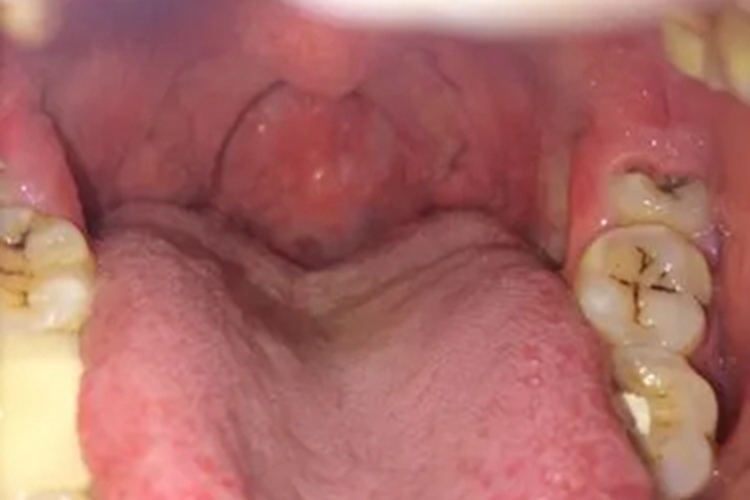

淋菌性咽炎可发生于咽后壁,皮损表现为局部充血、肿大,出现水疱样病变,疱壁紧张发亮,疱液相对澄清,基底黏膜微微发红,伴有轻微咽痛、吞咽不适等症状。